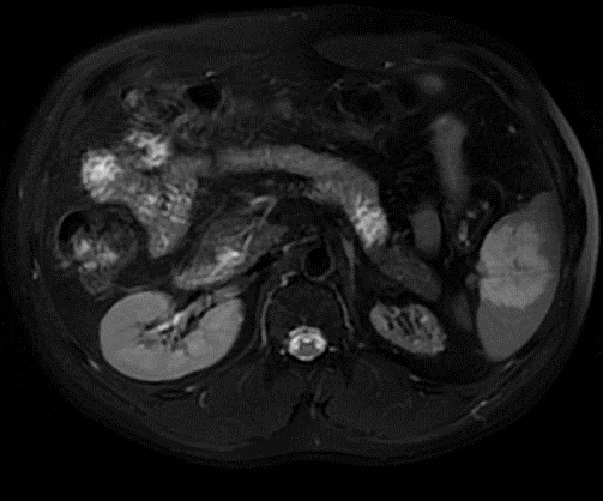

. Image

radiologique IRM d'une hemangiome da la rate

ponderee sur T2 FatSat . Aspect de masse hypersignal

, hetérogène de bien limité situé au milieu de la

rate . |